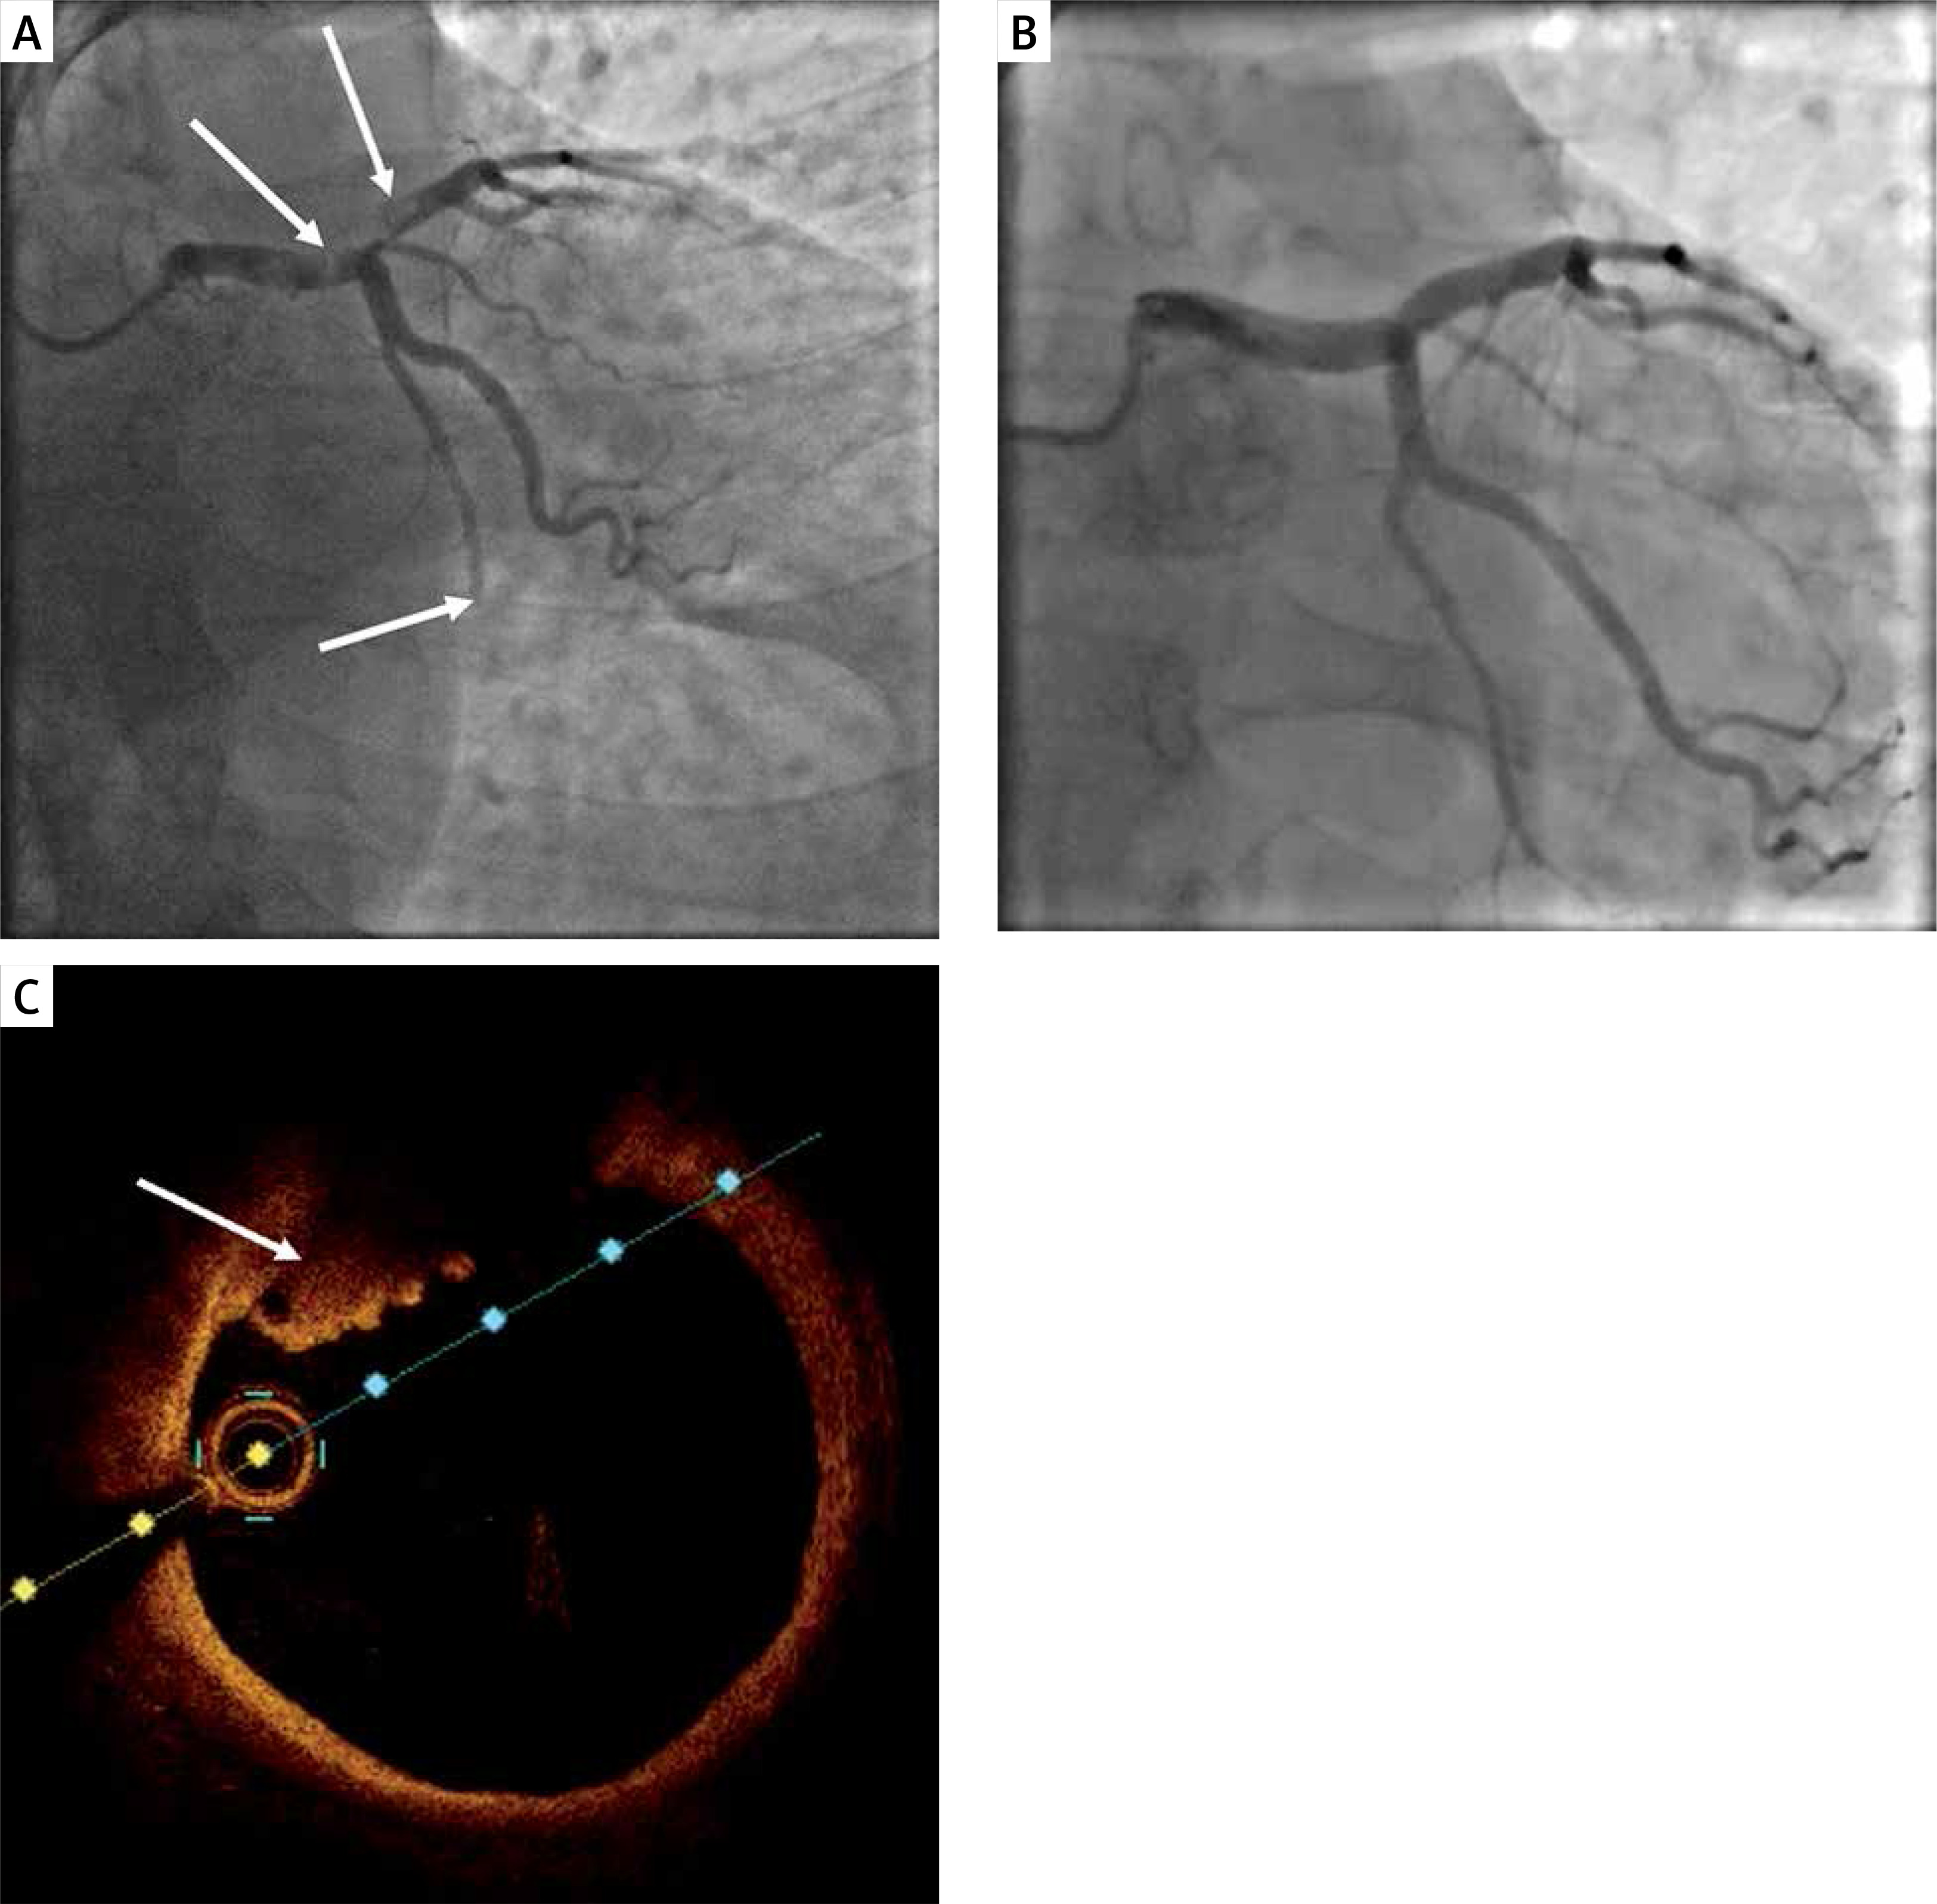

A – coronary angiography showing a massive thrombus in the distal left main coronary artery trunk, proximal left anterior descending and chronic total occlusion of distal left circumflex; B – coronary angiography eleven days after admission, no thrombus visible; C – optical coherence tomography showing a wall-mounted thrombus in the left main coronary artery trunk

Eleven days after admission, the second follow-up was performed, in which no LM thrombus was visible (Figure 1 B). OCT showed presence of a non-flow limiting fibrotic plaque (< 30% stenosis) in the LM and LAD with wall-mounted red thrombus and small elements of white thrombus (Figure 1 C). We did not observe plaque rupture, dissections or any other features of plaque instability. Taking the result into consideration the patient was qualified for conservative treatment without stent implantation.